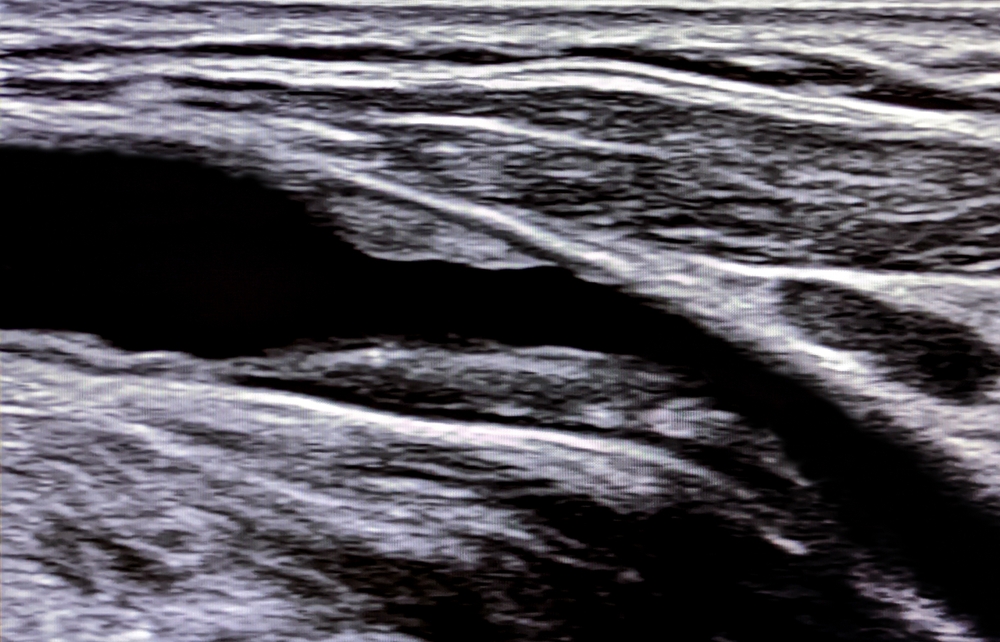

Blick ins Herz – präzise Diagnostik durch modernste Ultraschalltechnik.

Echokardiographie

(Herzultraschall inkl. Farb- und Gewebedoppler)

Die Echokardiographie ist eine schmerzfreie Ultraschalluntersuchung des Herzens. Sie ermöglicht eine genaue Beurteilung von Herzklappen, Herzmuskulatur und Blutfluss. Mithilfe von Farb- und Gewebedoppler lassen sich zudem Strömungsrichtungen und -geschwindigkeiten sichtbar machen. So können Funktionsstörungen, Klappenerkrankungen oder Herzmuskelschäden frühzeitig erkannt werden.